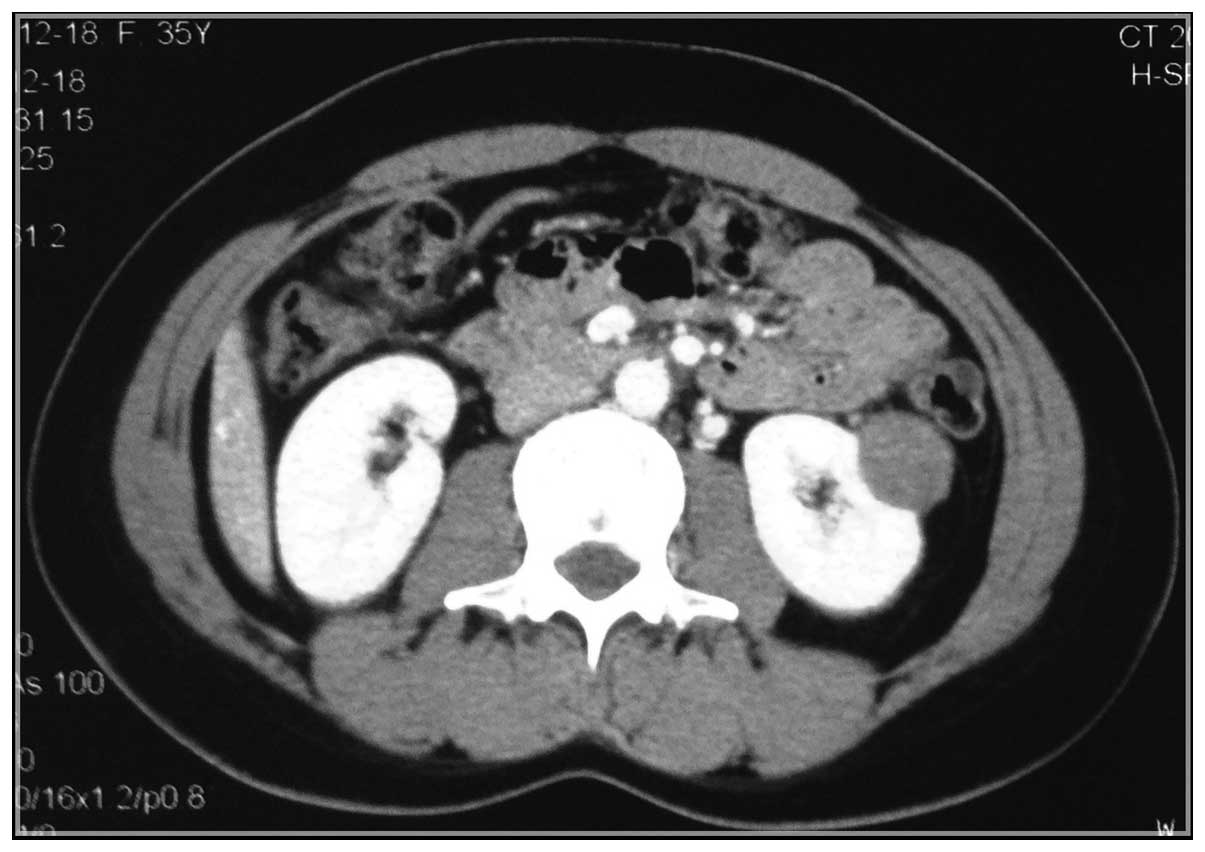

Clinical characteristics and pathology of thyroid‑like follicular carcinoma of the kidney: Report of 3 cases and a literature review

Thyroid‑like follicular carcinoma (TLFC) of the kidney is an extremely rare type of renal tumor, which has not been classified under a known subtype of renal cell carcinoma. It is histologically similar to the primary thyroid follicular carcinoma; however, the characteristics lack thyroid immunohistochemical markers. The aim of the present study was to illustrate the clinical characteristics of 3 new cases along with a review of the literature. The patients were compared with regards to gender, age, location and size of the tumor, imageology, morphology, immunohistochemistry and prognosis. According to the limited data, TLFC occurs mainly in young women and its clinical manifestations have no difference with other renal tumors. Its imageological features resemble a large spectrum of benign and malignant renal and extra‑renal conditions, which should be eliminated in the diagnostic process. Confirmed diagnosis depends on the examination of pathology and immunohistochemistry. Surgical ablation is the preferred therapeutic method. Currently, TLFC has a relatively good prognosis; however, this conclusion requires further cases and long‑term follow‑ups. Improving the understanding of TLFC can help avoid misdiagnosis and prevent inappropriate treatment.

Figure 2